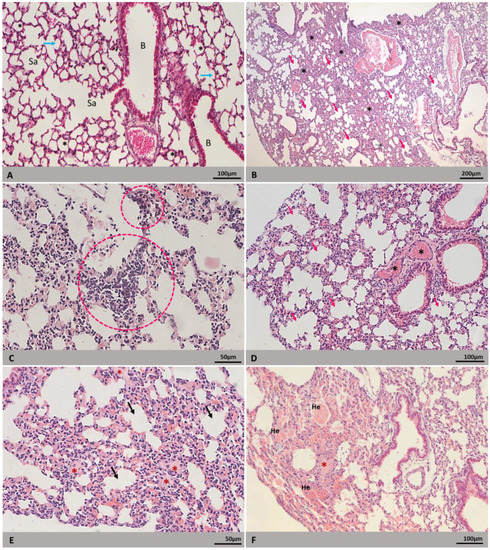

| Lung | Alveolar septum thickening | 10/10 (100) | 9/10 (90) | 19/20 (95) |

| Inflammatory infiltrate | 10/10 (100) | 9/10 (90) | 19/20 (95) | |

| Vascular congestion | 8/10 (80) | 6/10 (60) | 14/20 (70) | |

| Alveolar hemorrhage | 6/10 (60) | 6/10 (60) | 12/20 (60) | |

| Edema | 4/10 (40) | 4/10 (40) | 8/20 (40) | |